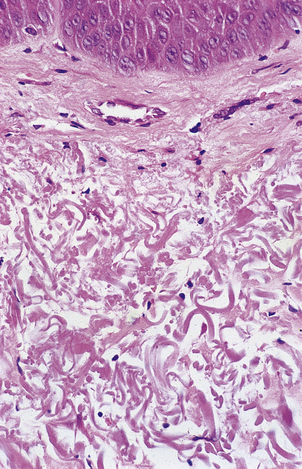

At a fairly gross level the elderly are identifiable from their wrinkled skin, loss of hair and sagging facial muscles, even if mental acuity is unimpaired (Fig. 12.5). Often the skin is also fragile, loses its youthful elastic recoil and is prone to bruising. Histologically the skin contains less collagen and less elastin, and what is still present is abnormal (Fig. 12.6), as judged by its biochemical properties. Both of these proteins are produced by fibroblasts so it is tempting to wonder whether fibroblasts alter with ageing. Research carried out on fibroblasts in culture has shown that cells from young individuals are capable of more cell divisions (about 50 in total) than are cells from elderly individuals.

image

Fig. 12.6 Elastosis in skin. Skin biopsy from the face of an elderly man showing masses of thick homogeneous fibres in the dermis resulting from chronic damage to the dermal collagen by sunlight. This causes the skin to appear wrinkled.

However, it is not enough to concentrate on the obvious; as in all clinical assessments we must consider the whole patient. A full assessment of the skin reveals that the wrinkling that we took to be a cardinal sign of ageing is most pronounced on the sun-exposed areas of the skin; those areas that have remained covered for most of the patient’s life look decades ‘younger’ by this criterion. So, what are we to conclude? Is ageing an environmental phenomenon induced by sunlight? This seems unlikely as it is hard to believe that the diffuse, multi-organ phenomena that we associate with ageing could all be produced by exposing the skin to ultraviolet light.